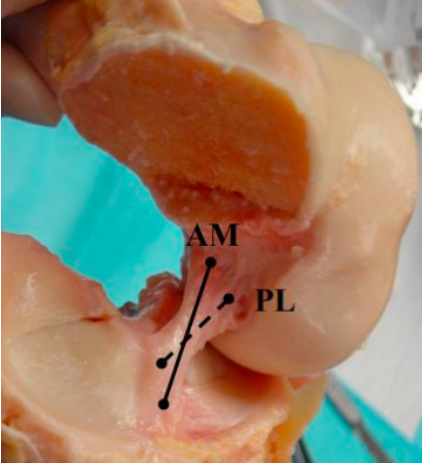

ACL 解剖

前交叉韧带起自股骨外侧髁的内侧面,斜向前下方,止于胫骨髁间隆起的前部。ACL 分为前内束(AM)和后外束(PL)。当屈膝 30° ~ 40° 时,前交叉韧带的张力最小。